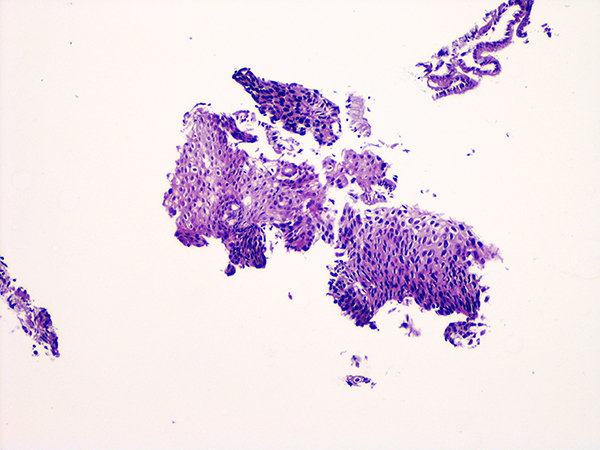

![]() Case 5

Soft Bx CIN 1

10x - Low Power |